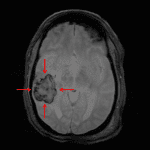

- Heterogeneous T1/T2 hyperintense lesion in the posterior right temporal lobe measuring 4.5 x 3.5 x 2 cm with associated susceptibility artifact and mild surrounding vasogenic edema with mild local mass effect resulting in partial effacement of the temporal horn of the right lateral ventricle

Acute intraparenchymal hematoma in the posterior right temporal lobe measuring 4.5 x 3.5 x 2 cm (calculated volume = 16 mL) with mild surrounding vasogenic edema and resultant mild local mass effect resulting in partial effacement of the temporal horn of the right lateral ventricle. No midline shift or evidence of herniation or hydrocephalus. Given location and the presence of multiple small additional acute infarcts, this is favored to represent hemorrhagic transformation of an infarct. Hypertensive hemorrhage is thought less likely given location.

Multiple small acute infarcts involving the bilateral cerebrum and left cerebellar hemisphere without additional sites of hemorrhagic transformation.

Multiple foci of susceptibility artifact involving the bilateral cerebral and cerebellar hemispheres as well as the midbrain and pons, compatible with sequela of prior microhemorrhage. While amyloid angiopathy could have this appearance, this would be atypical for patient age.